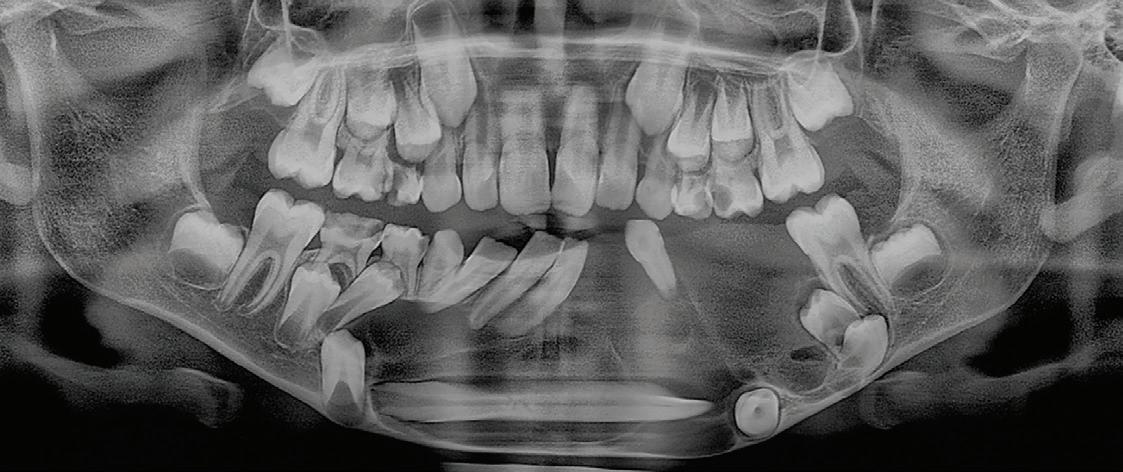

Chu44 35 M Swelling on left side of cheek FP,

Ferreira et al45 19 F Moderate headache, nausea, vomiting, left facial hypesthesia, low visual acuity FP, PP

Sohal et al46 24 M Massive swelling in right side of face FP

Linaburg et al47 50 F Massive swelling in left side of face Acanthomatous, FP

Abbreviations: F, female; FP, follicular pattern; M, male; NR, not reported; PP, plexiform pattern.

Chart. Distribution of maxillary ameloblastoma with extension into associated vital structures (N = 45).

Ameloblastomas of the jaws are commonly diagnosed in the third decade of life, and there is no sex predilection. However, ameloblastomas involving the sinuses and nasal cavities are more common in older men, as in the present case.49

Diagnosis of ameloblastoma requires clinical, radiographic, and histopathologic examinations. Clinically, sinonasal ameloblastoma can be associated with nasal obliteration, sinusitis and/or epistaxis, and less common signs and symptoms of facial swelling, headache, and tearing.42 Radiographically, primary sinonasal lesions frequently appear as radiopaque, solid lesions that fill the nasal cavity or sinus. In contrast, ameloblastoma of gnathic origin commonly presents as a unicystic or multicystic entity.42 However, this radiographic difference cannot be appreciated if the tumor involves all the vital structures and presents as a single lesion involving the maxillofacial region of that site. Histologically, ameloblastoma of jaws and sinonasal ameloblastoma have a similar appearance, commonly

Extension

Nasal cavity, orbital floor